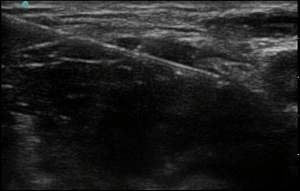

Figure 2: Sonoanatomy of the femoral nerve

Sonocharacteristics of the femoral nerve:

- Usually fairly superficial.

- Under the fascia lata (most superficial) and fascia iliaca (immediately adjacent to the nerve & separates the nerve from the artery).

- Lateral to the femoral artery and vein.

- Triangular shaped or oval/ flattened as the nerve fans out into multiple branches.

- Speckled and hyperechoic.

- Becomes less obvious as it branches out caudally.